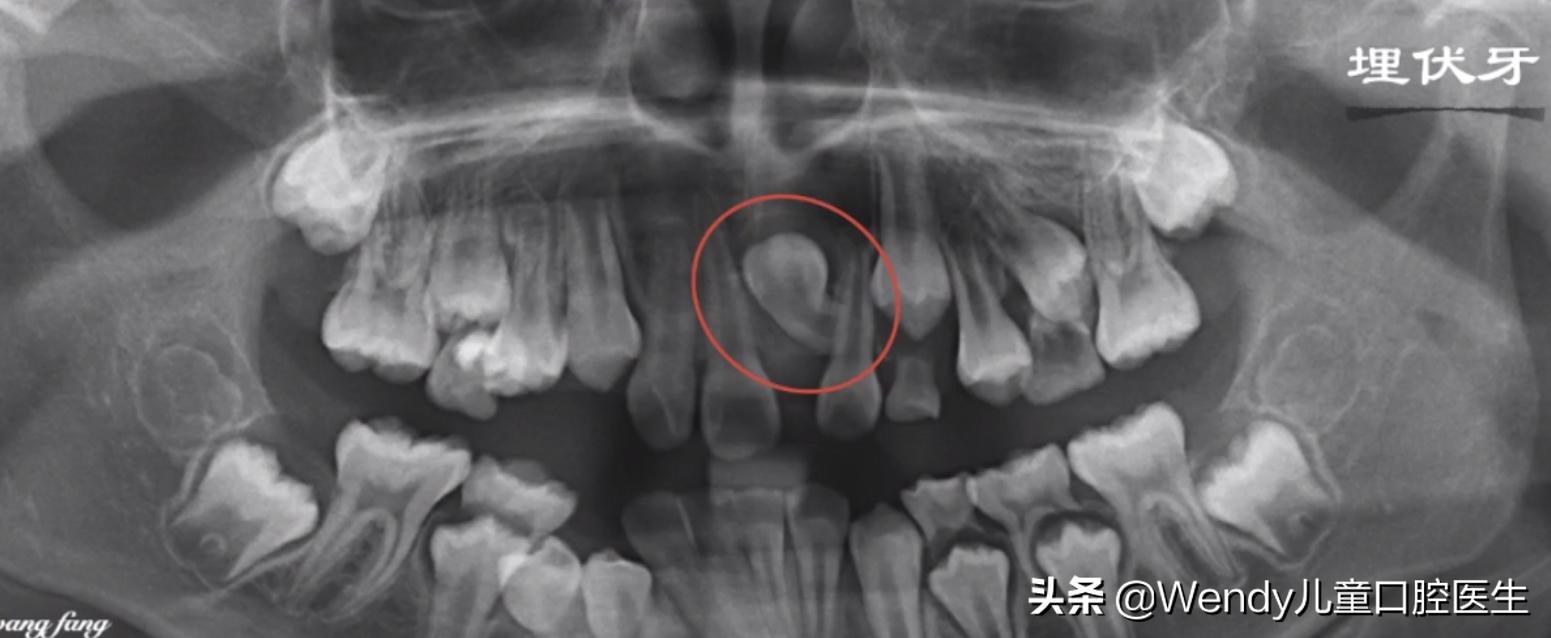

前天小泽妈带着小泽来看牙,乳牙按时掉了可惜新长出的恒牙怎么看都不对劲,形态怪异,一般这种情况首先考虑多生牙,建议拍摄全景片。果不其然,新长出的的确是多生牙,除外还发现颌骨里长了另一颗倒置的多生牙,这颗多生牙斜着挡在恒牙的上方,对恒牙萌出一定有影响,建议拔除。

其实像小泽孩子这种多生牙现象临床上真的挺常见了,有些多生牙是长出来被发现而即使拔除没有让恒牙受影响,可有些多生牙是埋伏在颌骨里暗地里对恒牙造成影响,所以换牙期的孩子定期看牙是很必要的,特别是7岁左右的孩子都建议拍摄一张全景片,能够很清楚知道颌骨下方恒牙胚发育的情况。

多生牙的确诊以及治疗拔除都需要在X线片下才能明确,常见的X线片有根尖片,全口曲面断层片和CBCT。

正因为多生牙多发生在换牙期,所以对于5-7岁的儿童进行一次X线片的拍摄是非常有必要的,便于早发现早诊断早处理。